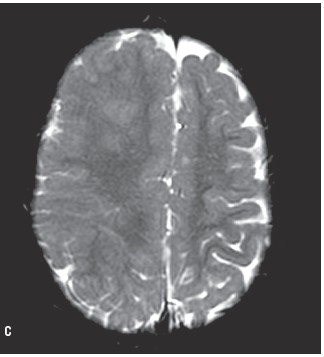

Dubbele cortex (corticale Laminaire heterotopias)(Afwijkingen ten gevolge van migratie)

Pachygyrie (lissencefalie)

- Afwijkingen ten gevolge van migratie

Polymicrogyrie, Agenese van het septum pellucidum, schizencefalie